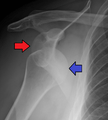

- An anterior dislocation of the shoulder

Anterior dislocation of the right shoulder. AP X ray